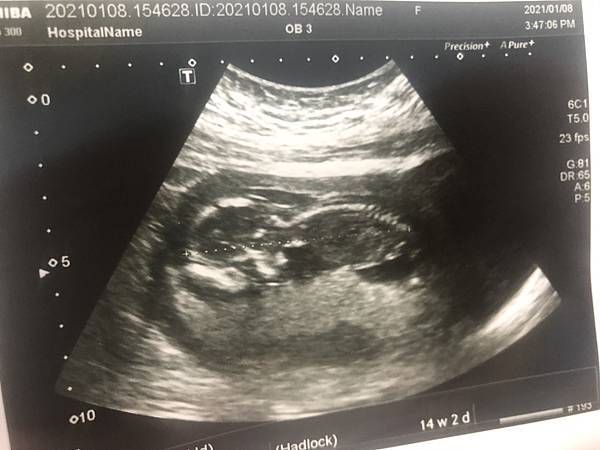

【第二孕期】舒適期來了《檢查-羊膜穿刺、高層次超音波、葡萄糖耐受試驗》

【第一孕期】天下的媽媽辛苦了!孕吐、嗜睡、腹脹、出血...關關過《檢查-脊髓性肌肉萎縮症SMA及X染色體脆折症Fragile X》